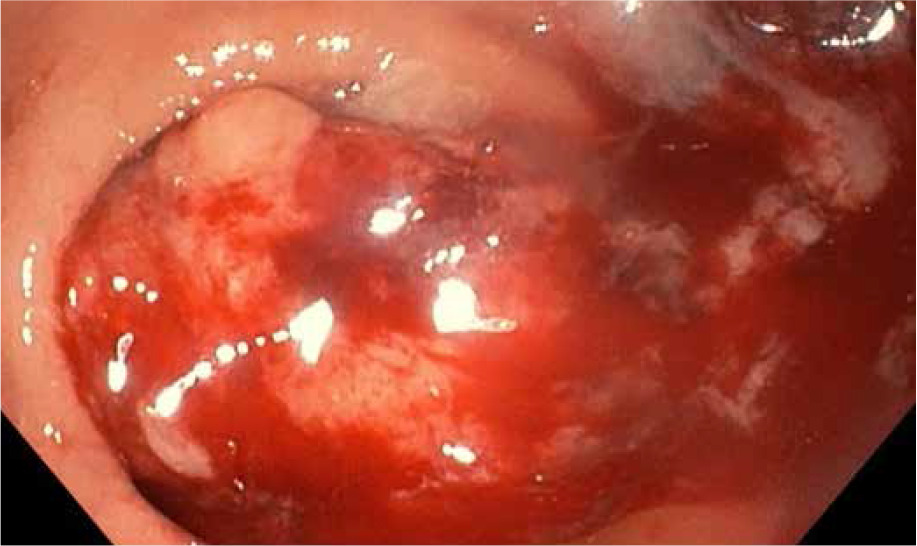

The patient underwent emergency surgery, and osteosynthesis was achieved by means of external bone fixation (Figure 3). Intraoperatively, a biopsy of the altered bone tissue from the fracture site was taken. The pathological examination revealed metastatic colorectal adenocarcinoma. During the hospitalization, a broad diagnostic work-up was undertaken. MSCT of the abdomen, thorax, and lower extremities was obtained and revealed rectal tumour with no signs of metastases apart from the osteolytic lesion in the fractured left tibia (Figures 4 A–C). Furthermore, a colonoscopy was done, and a circular mass in the upper rectum, about 12 cm from the anal verge, was found (Figure 5). Pathological examination of the tumour specimen obtained at colonoscopy confirmed a moderately differentiated primary adenocarcinoma of the rectum. The patient was presented at a multidisciplinary tumour-board, where it was decided to perform a resection of the primary tumour and a femoral amputation prior to chemotherapy.

Figure 4

A – Coronal plane of MSCT – osteolytic tibial lesion, B – Axial plane of MSCT – osteolytic lesion in the diaphysis of the left tibia covering almost all the diameter of the bone in this site, C – Axial plane of abdominal MSCT showing rectal mass